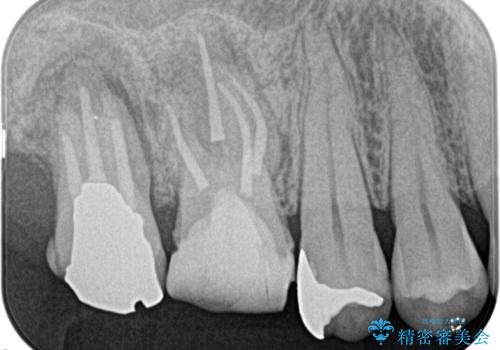

奥歯が痛い。精密根管治療〜オールセラミッククラウン

奥歯の根管治療~オールセラミッククラウン

根管治療の注意事項(リスク・副作用など)

- 根管治療により類似の全ての症例の問題が解決するわけではなく、症例はあくまでも一例です

- 根管治療により痛みや腫れがひかない事や、術後に痛みや腫れが生じる事、治療によるファイル破折やパーフォレーションなどの偶発症、術後の歯根破折を生じる可能性もあります